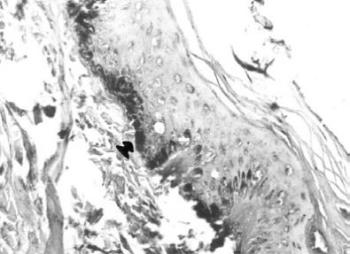

24. ábra. Sztereomikroszkópos felvétel a sípcsont bokanyúlványának csontszerkezetéről. 20× nagyítás

A sejtmarkerek olyan fehérjék, amelyek kizárólag bizonyos eredetű és funkciójú sejtekben fordulnak elő. A hámsejtek (egyéb markerek mellett) cytokeratinokat (CK) és epithelialis membrán antigént (EMA), tartalmaznak (21. ábra, 22. ábra). Az izomsejtek egyik markere a desmin, amelyet prostatában sikerült feltüntetnünk (23. ábra). Sok más sejtmarker (vimentin, lizozim, α-1 antitripszín stb.) kimutatása nem járt sikerrel. Gerszten és mtsa (1995) múmiák agyszövetét hisztológiai megfigyelésre alkalmasnak találták, a gliasejtek markerét, a GFAP-t (glial fibrillary acidic protein) nem tudták detektálni. A múmiaszöveteken végzett sikeres immunhisztokémiai azonosításokat a 6. táblázatban foglaltam össze.